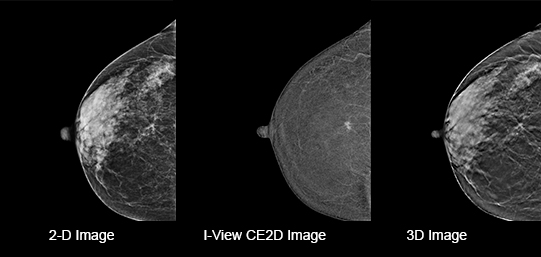

Eliminates Structural Background

Acquire a pair of high- and low-energy images in rapid succession. This allows for regions of abnormal blood flow to be displayed by subtracting the background breast parenchyma.

Contrast-enhanced mammography enhances visualization and may uncover hidden abnormalities – a crucial factor in reducing missed and or underdiagnosed cancers.